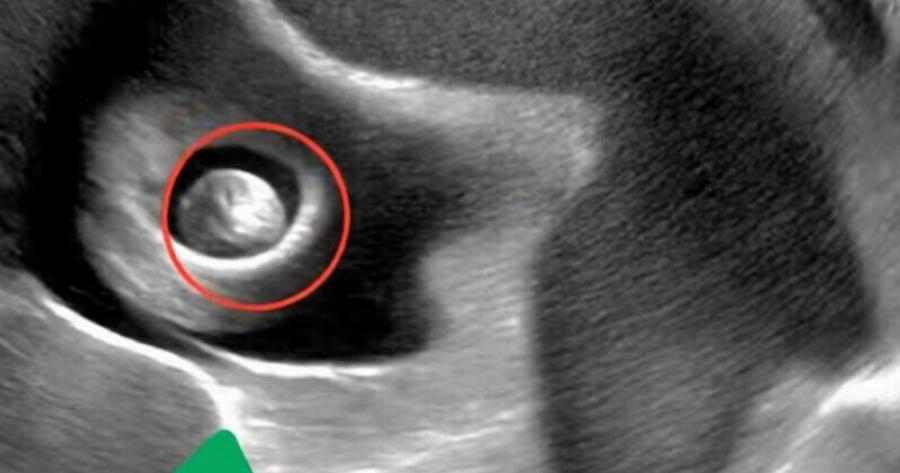

Λίγα λεπτά αργότερα, τα μάτια μας ήταν καρφωμένα στην οθόνη, μαγεμένα από την εικόνα που εμφανιζόταν. Το στομάχι μου σφίχτηκε: εκεί, μέσα στη Σοφία, υπήρχε ένα μικρό, γυαλιστερό νόμισμα.

Δυσκολευόμουν να αναπνεύσω. Πώς; Πότε; Γιατί; Ένα κύμα φόβου, ενοχής και σύγχυσης με πλημμύρισε. Τα δάκρυα θόλωναν την όρασή μου ενώ ο γιατρός εξηγούσε ήρεμα την κατάσταση. Με καθησύχασε: μερικές φορές τα παιδιά καταπίνουν από περιέργεια μικρά αντικείμενα. Μπορεί να είναι επικίνδυνο, αλλά με προσεκτική παρακολούθηση όλα μπορούν να πάνε καλά. Η Σοφία θα χρειαζόταν μια διαδικασία για την ασφαλή αφαίρεση του νομίσματος. 😭